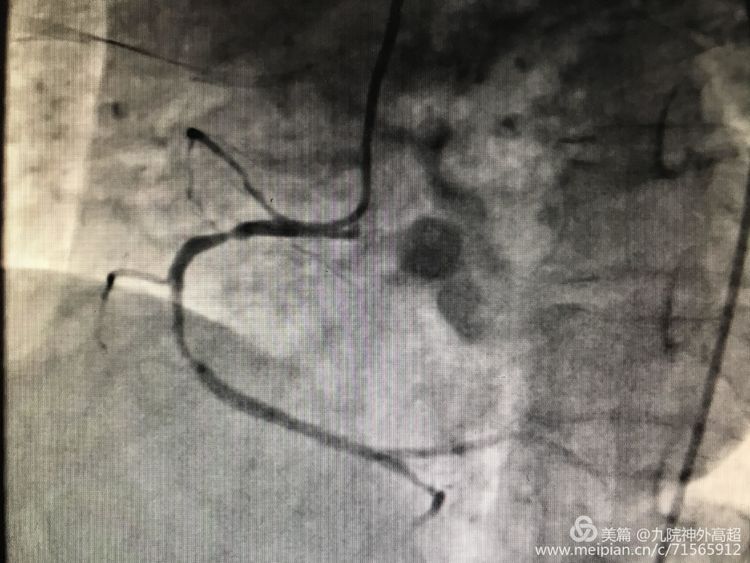

用医术用爱心 做忠实健康守护者

5月29日上午在医护人员的护送下、患者王师傅康复出院! 63岁的王师傅,以“糖尿病足坏疽伴感染、2型糖尿病 高血压病 3级 很高危”入住我院内分泌科。行糖尿病系统治疗... -